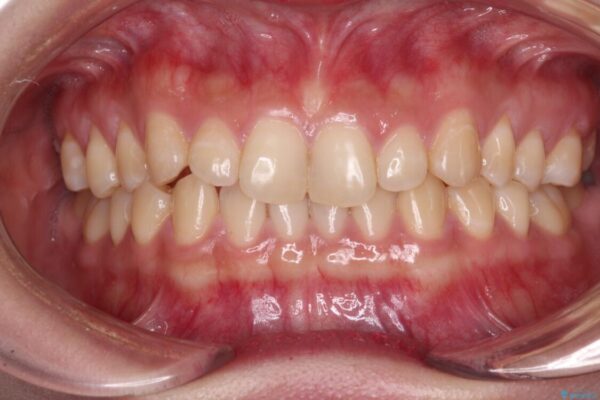

治療途中

• 治療途中の奥歯と矯正治療の後戻り インビザライン・ライトによる矯正治療 治療途中画像